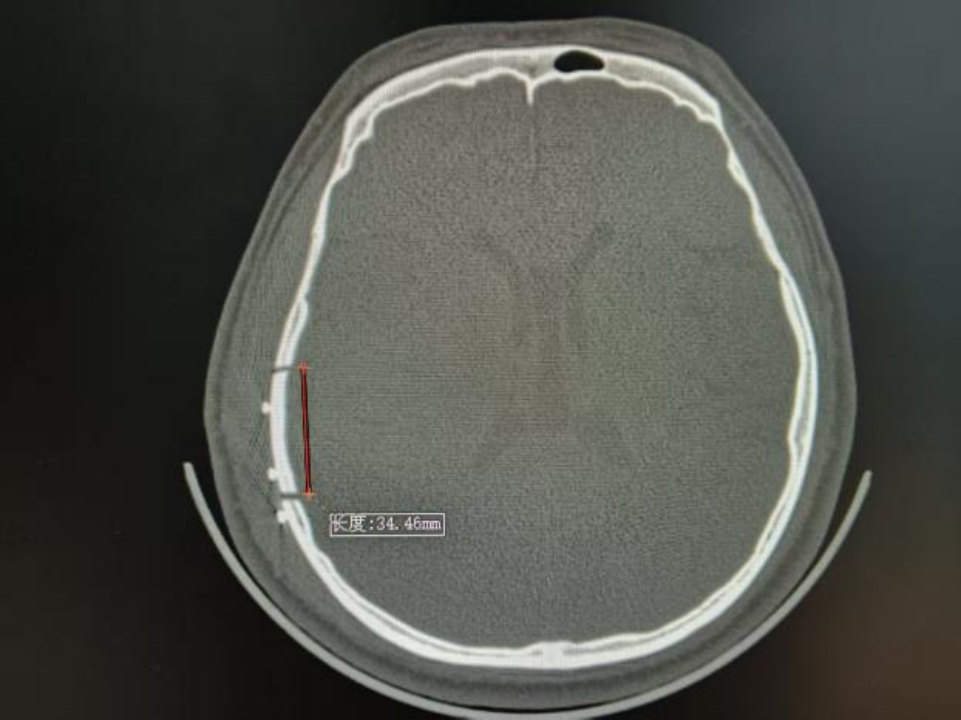

△术前颅脑CT

近期,北大人民青岛医院神经外科团队在北京大学人民医院神经外科专家刘波带领下,常态化开展神经内镜下硬脑膜外血肿清除术。其中一位19岁的年轻小伙,驾驶摩托车不慎摔伤,伤后头痛、头晕、恶心,头痛呈进行性加重,逐渐开始出现意识障碍,到青岛医院急诊行颅脑CT检查后证实为创伤性硬脑膜外血肿,神经外科团队予以急症状态下神经内镜下硬脑膜外血肿清除术手术治疗,目前患者已经康复出院。